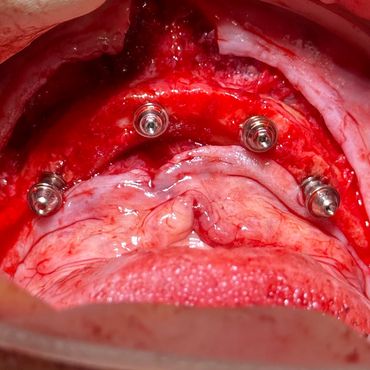

Over the years, I’ve performed 50,000+ extractions and placed more than 3,000 implants, including over 300 full arch immediate loading cases. Every case has taught me something new, and reinforced my belief that surgical dentistry is where I can make the biggest difference.

Guided bone regeneration (GBR), bone core techniques, and autogenous bone harvest

Advanced grafting solutions: Split Bone Block technique and 3D Bone Builder

Includes lab fees and implant components. Delivered with a fully digital workflow using IOS and photogrammetry. Treatment protocol: All-on-4 with same-day PMMA, second printed PMMA, and final zirconia hybrid bridge